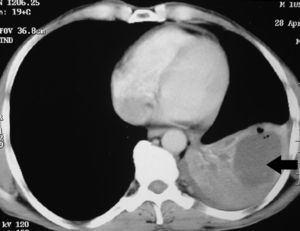

Caso clínicoUn hombre de 45 años de edad solicitó una valoración de su médico de cabecera tras los antecedentes de esputo hemoptoico y tos seca de un mes de duración. Por consiguiente, fue derivado al hospital de los autores después de que la visión posteroanterior de una radiografía de tórax (fig. 1) mostrara la presencia de un quiste en el lóbulo inferior izquierdo (LII). En la valoración inicial se obtuvo una anamnesis en la que el paciente refirió antecedentes de tabaquismo de 26 paquetes/año. También refirió que en la radiografía de tórax previa, efectuada 2 años antes en una revisión médica anual sistemática, no se encontraron anomalías. Tampoco tenía antecedentes de enfermedades respiratorias previas. La exploración física reveló una disminución de la intensidad del murmullo vesicular sobre las áreas inter e infraescapulares internas. La tomografía computarizada (TC) de tórax reveló un quiste de forma irregular y pared fina, junto con una disminución generalizada de la atenuación en el LII (fig. 2). Se programó una broncoscopia de fibra óptica (BFO), pero el paciente se perdió para el seguimiento. Más tarde regresó tras un período de 2 meses, en vista de los síntomas crecientes. Se asociaban con anorexia y una pérdida de peso de 4kg. La TC repetida de tórax (fig. 3) demostró el colapso completo del LII que contenía un quiste lleno de líquido, colapsado (flecha negra). También se observó una masa en la región hiliar izquierda con la pérdida de los planos de grasa en la aorta descendente. En la BFO (vídeo 1) se observó una proliferación en el bronquio principal izquierdo a 4cm de la carina que ocluía por completo el bronquio principal del LII. En la biopsia endobronquial se demostró la presencia de un carcinoma de células escamosas (fig. 4). Más tarde, el paciente recibió 4 ciclos de quimioterapia con docetaxel y cisplatino, seguidos de radioterapia torácica (secuencial) como tratamiento combinado para un cáncer de pulmón no microcítico en estadio IIIB. Más adelante se demostró la progresión de la enfermedad, y falleció alrededor de 10 meses después del diagnóstico.